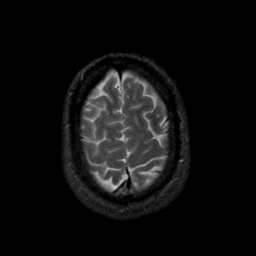

MR Study #9, April 14, 1991 -- Slice #43

[Home][Help][Clinical][Tour 1][Tour 2] Slice 43